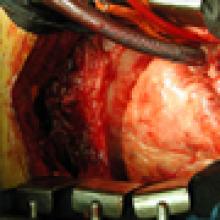

An anterolateral left ventriculotomy is made through the area of infarction parallel to and two centimeters away from the left anterior descending artery. Stay sutures can be placed through the edges of the ventriculotomy to maintain an open visual field. The interventricular septum, area of infarction, and site of rupture are visualized (Figure 3).

The necrotic portion of the septum is inspected but no debridement is necessary. The defect is not closed rather it is excluded from the ventricular cavity (Figure 4).